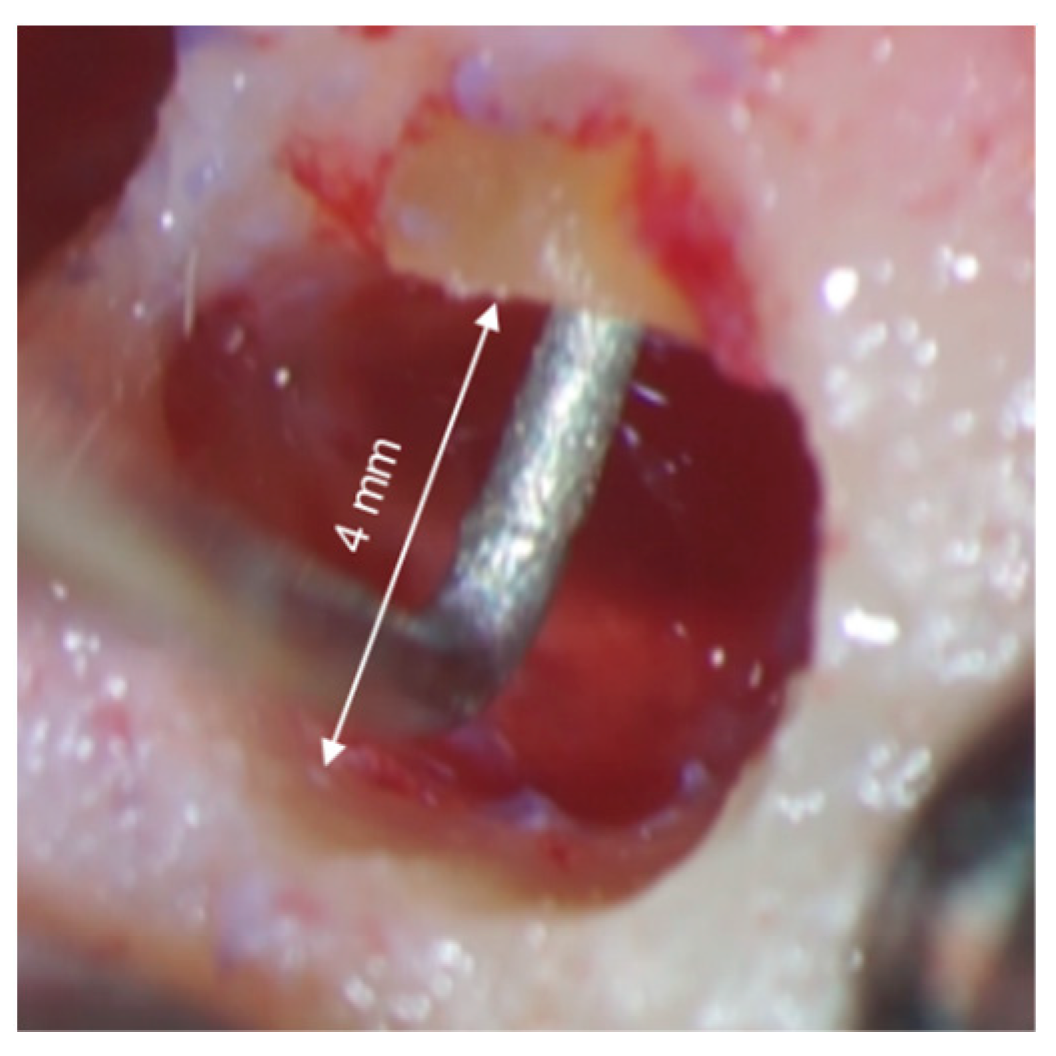

3.3. Root-End Resection

3.4. Root-End Preparation